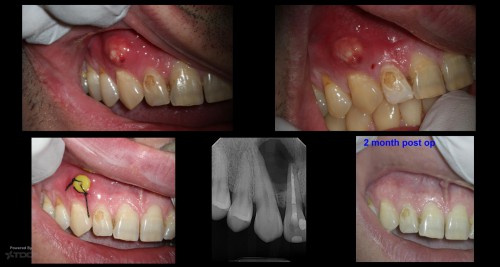

The talon cusp saga

15 yom with buccal swelling associated with tooth # 10, multiple visits with Calcium hydroxide, […]